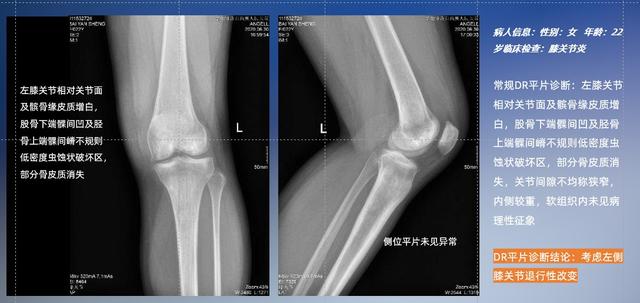

以膝关节疾病检查为例,膝关节在解剖学意义上是一种较为复杂的最大关节,由胫骨上端、股骨下端及髌骨组成。在股骨与胫骨的关节面之间存在两块半月板,分别处于内侧、外侧。膝关节的运动主要为伸、屈,在半屈位时可进行小幅度的旋外、旋内运动。随着现代人们体育生活以及肥胖的增加,膝关节疾病出现高发趋势,特别是关节磨损、膝关节炎与骨关节炎等关节退行性改变,长时间的内翻负荷会造成内侧关节软骨、骨性关节面的磨损。目前针对此类疾病的检查主要为平片下的负重位检查、CT检查以及MRI检查,相较于非负重位检查,负重位检查能更加真实反映膝关节结构中胫骨、股骨、髌骨实际对位关系和关节面的形态特征及关节间隙大小,对膝关节骨关节病诊断准确率高。

普通平片扫描与WR-3D扫描前后诊断结果对比

在负重位状态下,数字化X线三维扫描与重建,能够更好的呈现受检者关节受力改变的状态。德赢VWIN科技创新的WR-3D动态三维影像重建系统,通过数字化X线摄影完成三维扫描并重建三维影像信息,包括断层图像重建、MPR多平面重建、MIP重建以及VR体绘制。其扫描时间短,剂量相较于CT设备大幅缩减,同时成本更低,在临床诊断以及医疗方案制定中具有极大的价值意义。而相较于普通平片下的负重位扫描,负重位动态三维影像重建技术能够避免二维状态下的组织结构重叠、密度分辨率不足、组织解剖结构难以分辨等问题。WR-3D支持多角度的三维观察,能全面的呈现被检查部位在多个角度下的三维影像信息,极大的降低了二维负重位检查带来的漏诊率。